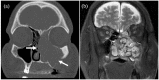

Sinonasal organizing hematomas are benign lesions often mistaken for malignancy due to their aggressive appearance on diagnostic imaging and endoscopic findings that favor advanced disease. The destructive nature of this pathology paired with the rarity of the presentation often results in diagnostic deception that may escalate intervention planning and affect discussion of prognosis with patients. Herein, we present a case of a 56-year-old male with left-sided nasal obstruction and daily epistaxis, where computed tomography imaging revealed heterogeneous opacification of the left maxillary sinus, erosion of the left inferior orbital wall and extension into the nasal cavity. Although clinical and radiographic presentations of sinonasal organizing hematomas can be managed definitively with endoscopic intervention, there is a need to increase awareness of this entity among clinicians to improve our prognostic counseling with patients.